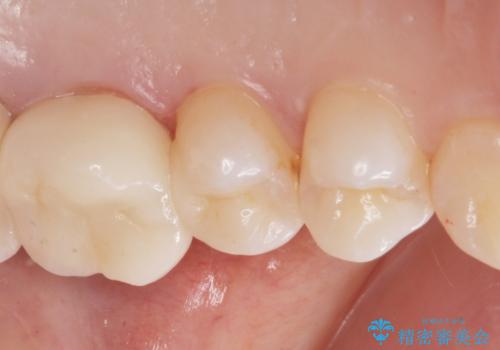

銀の詰め物を拡大鏡下で取り除き、う蝕がないことを確認してから

ZrCrの被せ物で治療を行いました。

また、一つ手前の歯に小さな虫歯があったため

e-maxインレーでの治療を行いました。

- ジルコニアクラウン・仮歯・e-maxインレー 19.8万円費用は治療当時の料金となります